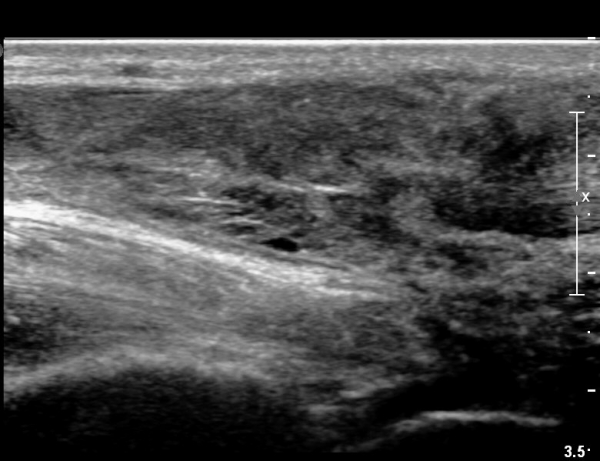

³»Ãø ºñº¹±Ù Á¾´Ü¸é°Ë»ç¿¡¼­ ³»Ãø ¹èº¹±Ù ¸»´ÜºÎ ÆÄ¿­°ú °¡Àڹ̱٠½ÉºÎ¿¡ ¼ö¾×Àú·ù°¡ °üÂûµÊ(»çÁø 1, 2).

¾ÆÅ³·¹½º°Ç Á¾´Ü¸é°Ë»ç¿¡¼­ ¾ÆÅ³·¹½º°Ç ¸»´ÜºÎ¿¡ ¾ÆÅ³·¹½º°ÇÀÇ Àú¿¡ÄÚºÎÁ¾, ±¹¼ÒÀû ¿¬°á¼º ¼Ò½Ç,